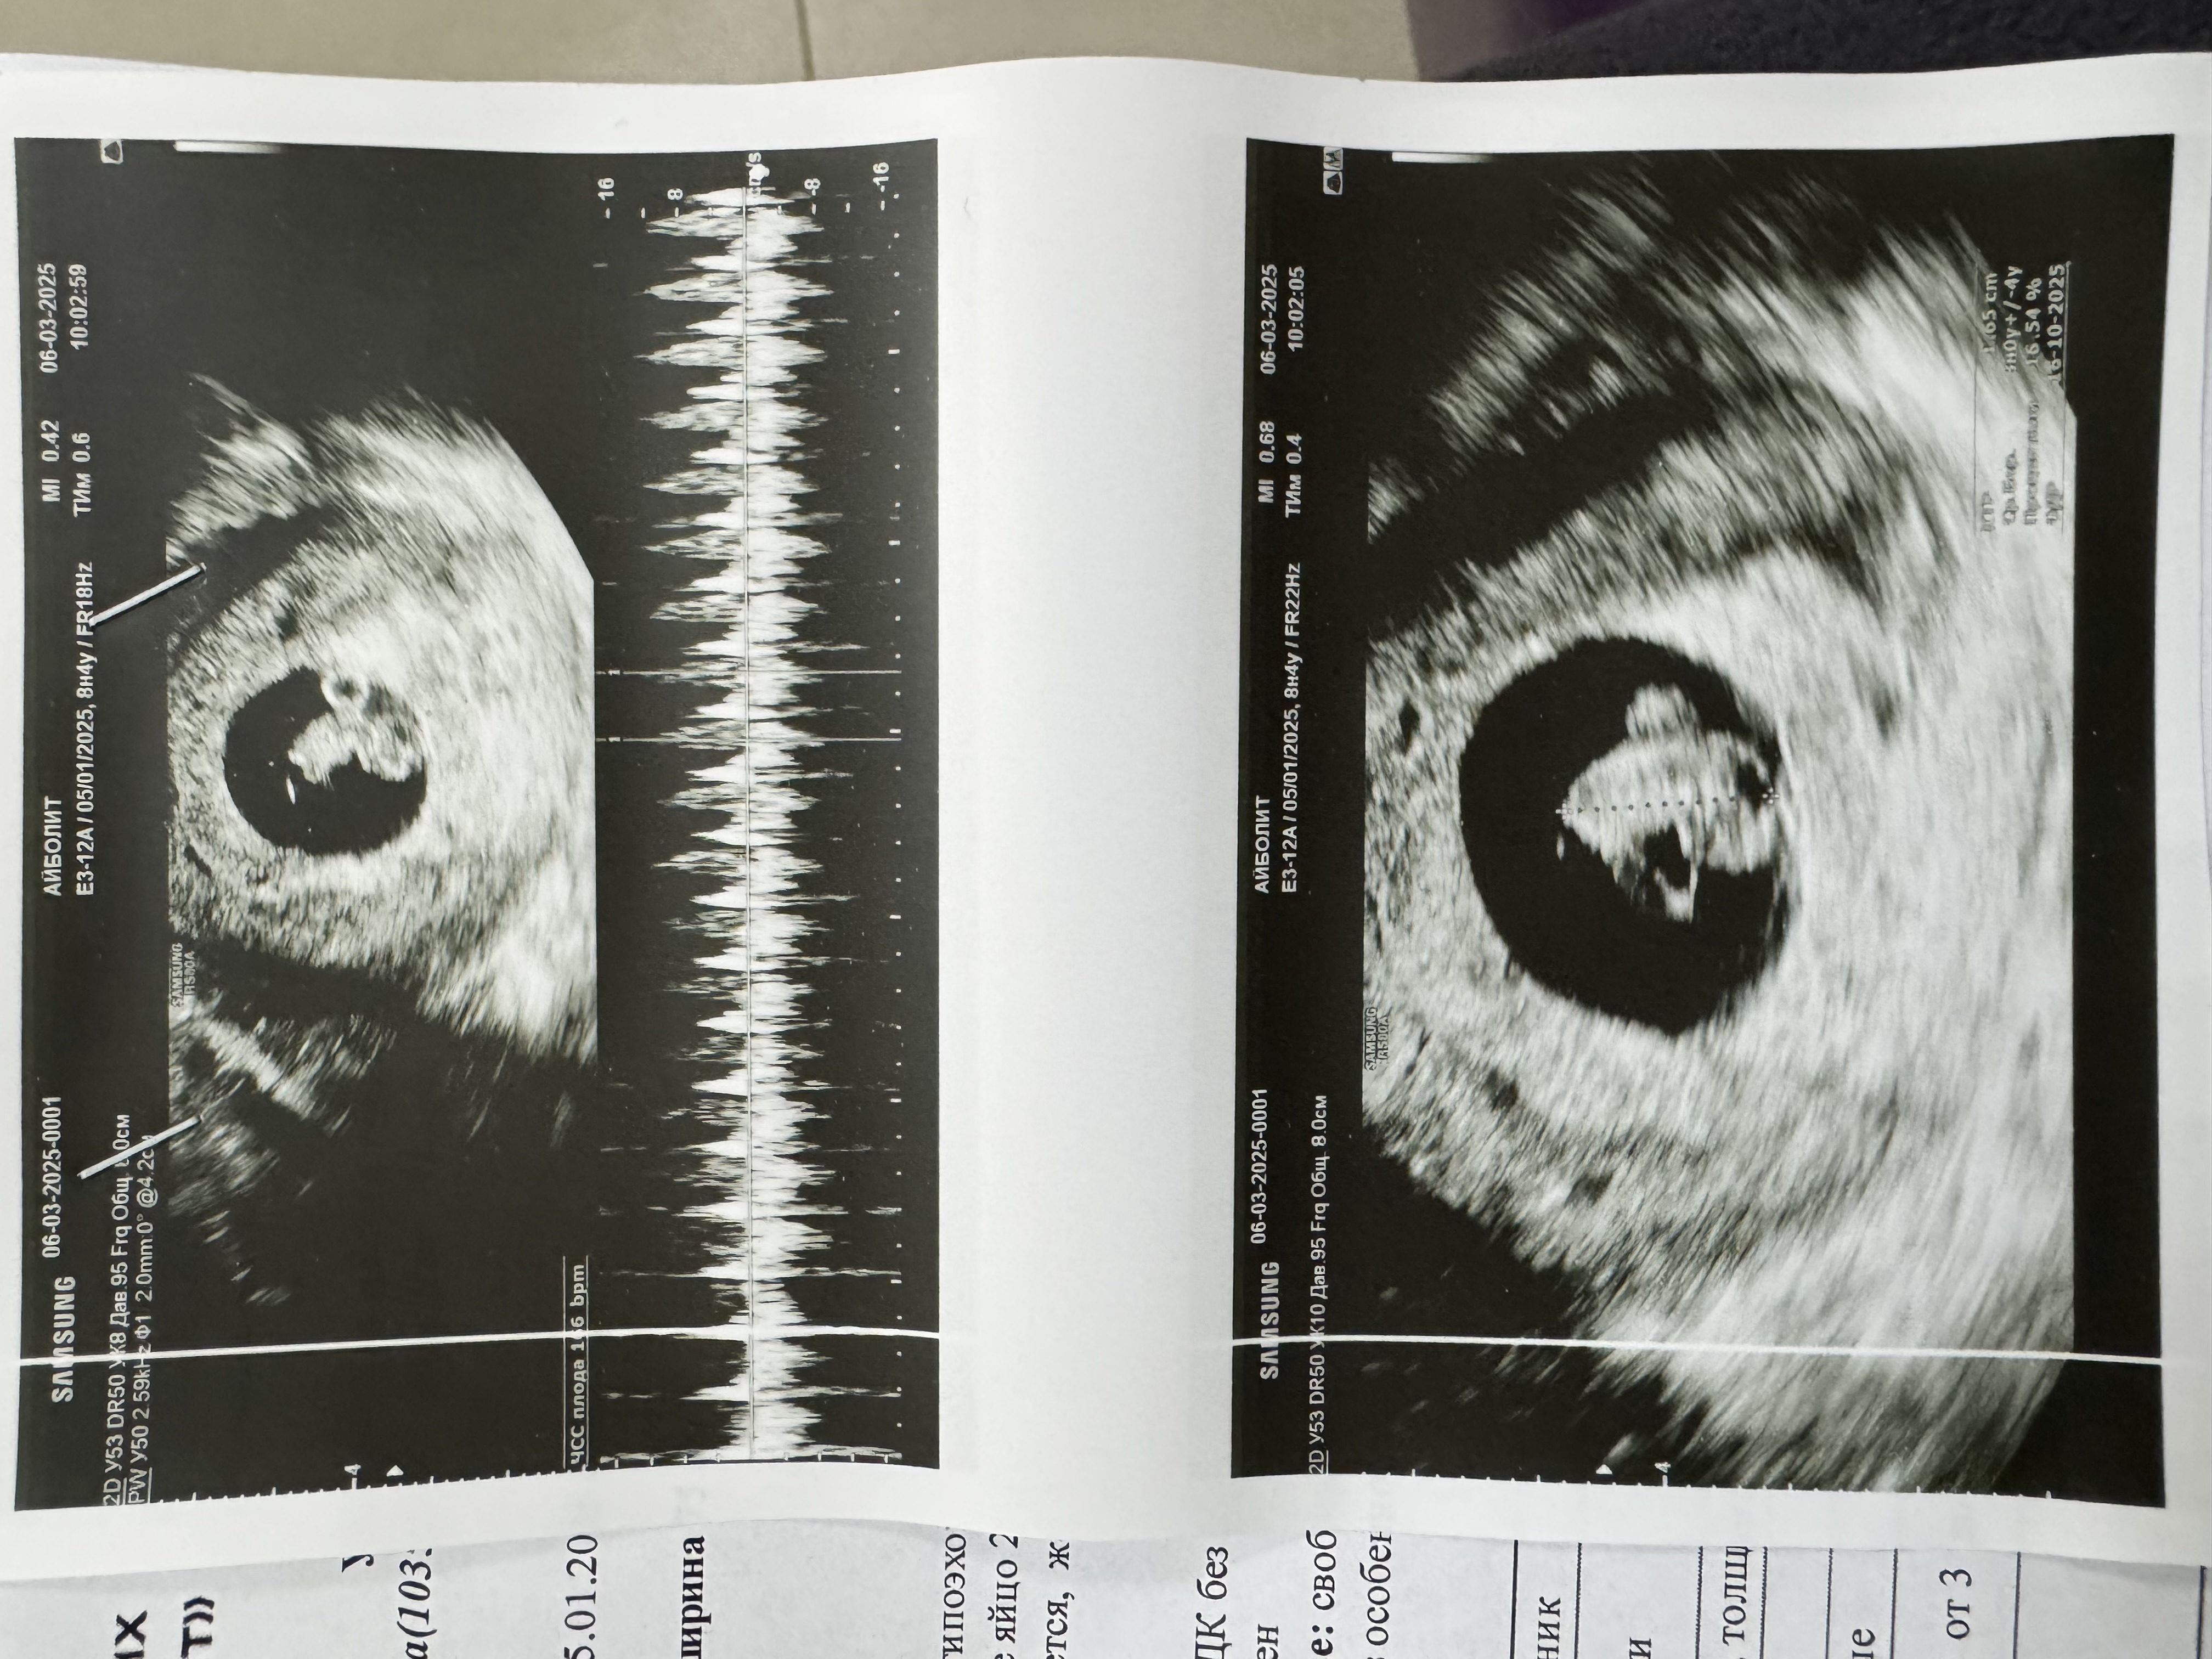

УЗИ в 8.4

Девушки, привет!) Сходила сегодня на узи, тк было какое то тревожное состояние, все таки зб и выкидыш в прошлом дают о себе знать. По узи все хорошо, врач наругала, сказала меньше тревожиться и вставать уже на учет. Пойду на следующей неделе) По узи вроде все хорошо, сердечко бьется, все показывали на большом мониторе, такая креветочка 🍤😍 Даже увидела как пошевелился, тут я даже прослезилась 🥹